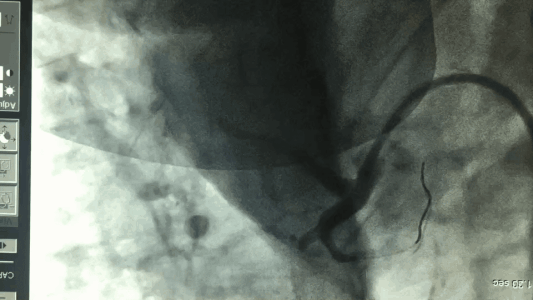

对于急性心肌梗死的病人,我们要及时识别,尤其是有高血压、糖尿病、高血脂等基础疾病的人群,当突然出现胸骨后持续性的剧烈疼痛,且含服硝酸甘油不能缓解时,需要警惕,立即服用负荷剂量阿司匹林和氯吡格雷,送去医院,完善心电图、心肌损伤酶谱检查,在发病12小时内可行直接冠状动脉介入治疗(急诊PCI)以开通闭塞的血管,必要时可安置支架,恢复血流,减少死亡。同时,注意并发症的处理,术后按医嘱服用药物。